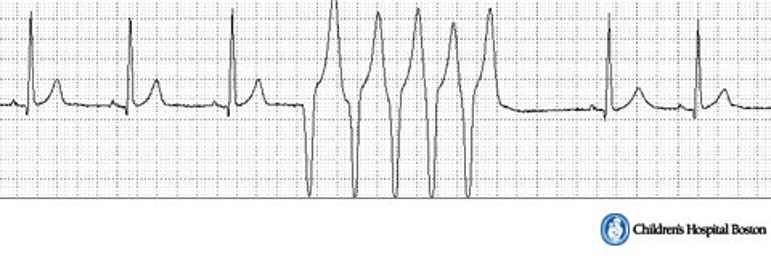

This ECG has no discernable P wave and a wide bizarre QRS complex. There is irregular rhythm with normal HR, and a large T wave in opposite direction of QRS complex.

There is a Compensatory pause following VPC

This arrythmia is caused by Irregular rhythm with normal HR

Large T wave in opposite direction of QRS complex

Compensatory pause following VPC

Ventricular Premature Contraction